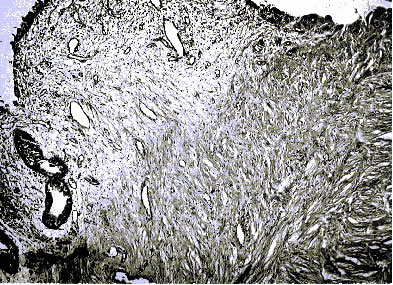

14 сутки (Неполный сетчатый (перимускулярный)

склероз)